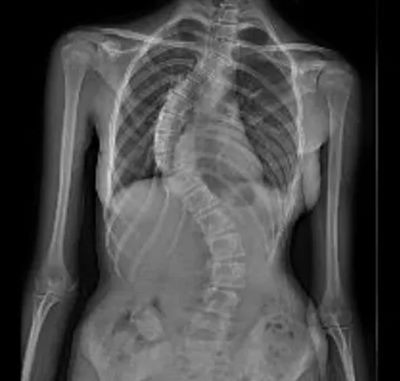

▲ 术前X线

影像学显示,小范胸椎侧弯达58°,伴有明显椎体旋转与胸廓变形。肺功能提示呼吸已受影响。闫鹏主任解释道:“Cobb角超过45°–50°且骨骼未成熟时,侧弯很可能会继续加重。小范正处于生长高峰,侧弯角度大、进展快,支具已无法控制,手术是当前唯一有效的治疗方法。”

历经6个小时精细操作,手术圆满成功。术后X光显示,小范的脊柱侧弯从58°矫正至8°,矫正率达86%,外观显著改善,身高也从158厘米增至162厘米。